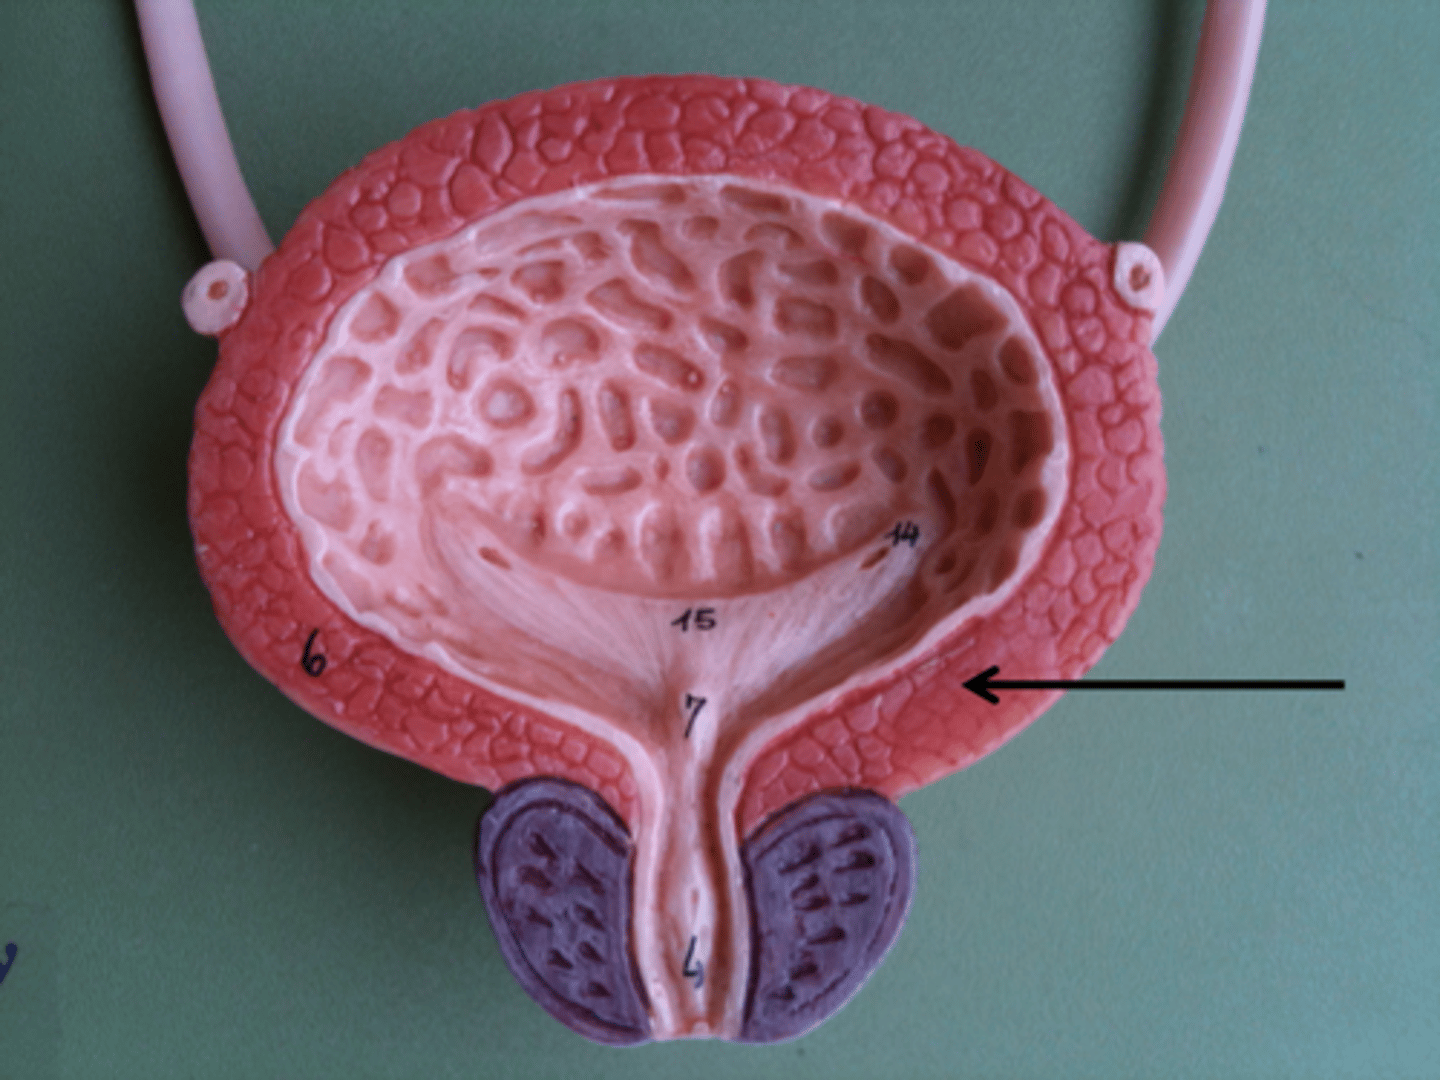

urinary bladder

urinary bladder

detrusor muscle

layer

internal urethral sphincter

bladder neck

external urethral sphincter

ureteric orifice

trigone of bladder

rugae

Urethra